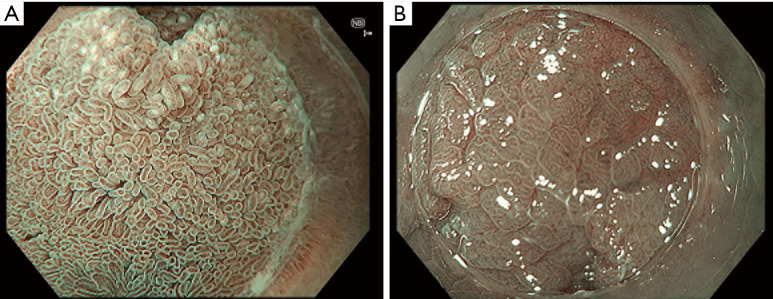

Background and objective: Coeliac disease (CD) is a common autoimmune disorder triggered by gluten consumption in genetically predisposed individuals. CD is characterised by chronic inflammation in the small bowel mucosa with an influx of lymphocytes, followed by crypt hyperplasia and villous atrophy. The gold standard test to diagnose CD is endoscopy with duodenal biopsies. However, variations in practice between endoscopists can lead to missed diagnoses. This review aims to discuss the role of endoscopy in the diagnosis of CD, highlighting the performance measures of endoscopy in CD and the advancement in endoscopic techniques for the optical diagnosis of villous atrophy.

Key content and findings: We provide an up-to-date assessment of the diagnostic accuracy of endoscopic markers of CD and the performance of enhanced endoscopic imaging to identify villous atrophy during endoscopy. We propose a set of benchmarks for endoscopy in CD and discuss the potential role of artificial intelligence (AI) in the endoscopic diagnosis of CD.